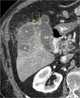

Pericholecystic abscess

Cholecystitis is inflammation of the gallbladder. Symptoms include right upper abdominal pain, nausea, vomiting, and occasionally fever. [Source: Wikipedia ]